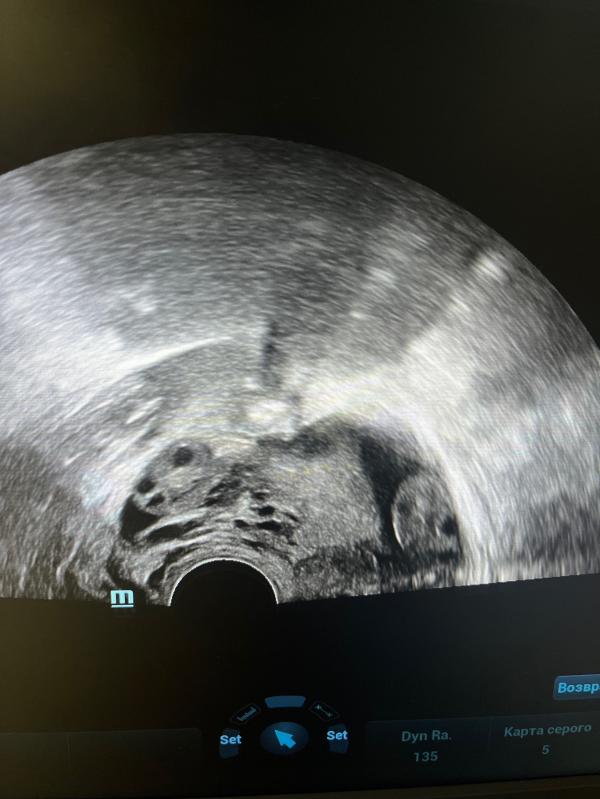

П.с. На фото два яичника в заднем своде и жидкость в позадиматочном пространстве, женщина здорова ❤️

Боли внизу живота во второй половине цикла связаны с овуляцией и вызваны жидкостью из овулируюшего яичника, которая скапливается в дугласовом пространстве (карман между маткой и прямой кишкой) и раздражает рецепторы брюшины.